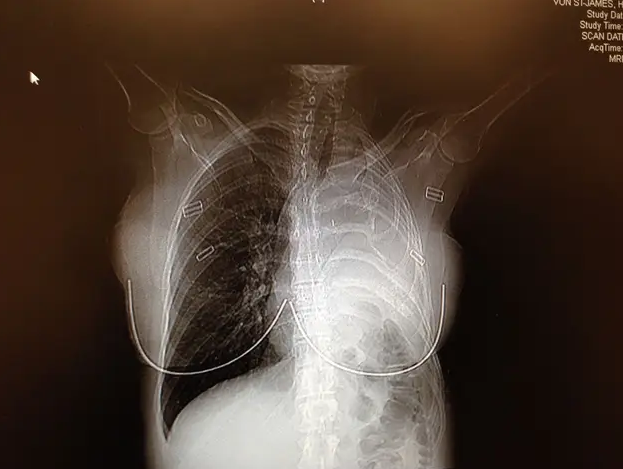

Nakon što se porodila carskim rezom, frizerka po zanimanju, otišla je kod ljekara koji ju je podvrgnuo CT skeniranju, otkrivajući tumor u blizini pluća.

U roku od dvije sedmice, doktori su joj dijagnostifikovali pleuralni mezoteliom, rijedak i agresivni rak povezan s izloženošću azbestu. Dali su joj 15 mjeseci života, prenio je Mirror.

Godine 2006. podvrgnuta je složenoj operaciji koja je uključivala uklanjanje lijevog plućnog krila, rebra, pleure (sluzokože koja oblaže pluća), dijela dijafragme i sluznice srca.